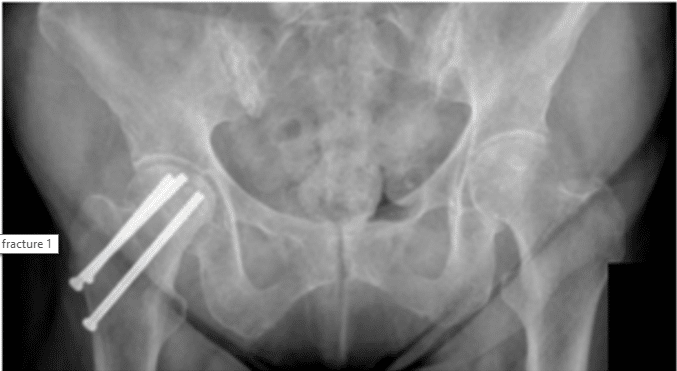

Patient is a 68 year old female who came in complaining of right hip pain after having a surgery to fix a previous right hip fracture. Patient brought in x-rays to review, as shown below, and it was determined that it was the hardware from the previous surgery that...